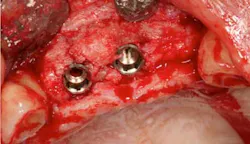

Fig. 7